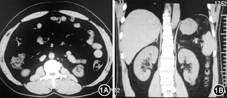

辅助检查:尿糖(4+)、尿蛋白(3+)、隐血(2+)、尿pH为6.0;血尿素氮5.23 mmol/L,肌酐88.0 μmol/L,尿酸165.6 μmol/L;TC 8.86 mmol/L、LDL–C 6.40 mmol/L、TG 1.75 mmol/L;心肌酶及肌钙蛋白T、肌酸激酶同工酶、肌红蛋白均正常;B型利钠肽前体491.60 ng/L;血pH 7.466。随机血糖:24.9 mmol/L,糖化血红蛋白(HbA1c)10.0%;空腹血清C肽1.51 μg/L、餐后2 h血清C肽4.32 μg/L;糖尿病相关抗体阴性。4次测血钾分别为3.19 mmol/L、3.32 mmol/L、2.86 mmol/L、2.65 mmol/L;2次24 h尿钾(增高)分别为:42.63 mmol/L(同步血钾3.19 mmol/L)、33.53 mmol/L(同步血钾2.65 mmol/L)。肾素活性:74.5 ng·L–1·h–1 (卧位正常值1.5~23.3 ng·L–1·h–1),醛固酮486.9 ng/L(卧位正常值12~150 ng/L)。醛固酮卧立位试验:卧位醛固酮182.37 ng/L、肾素活性:194.6 ng·L–1·h–1;立位醛固酮355.91 ng/L、肾素活性:111.2 ng﹒L–1·h–1。甲状腺功能正常;血清皮质醇测定8:00为216 μg/L (参考值50~280 μg/L),16:00为150μg/L,0:00为232 μg/L。血清促肾上腺皮质激素(ACTH)9.38 ng/L(8:00参考值5~60 ng/L)。3次24 h尿儿茶酚胺分别为184.95、54.61、73.00 nmol/24h(参考值94.5~238.3 nmol/24 h),尿香草扁桃酸分别为41.78、24.77、31.94 μmol/24 h(参考值<68.6 μmol/24 h),尿肾上腺素分别为:73.57、35.77、40.88 nmol/24 h(参考值12.5~70.4 nmol/24 h),尿去甲肾上腺素分别为111.38、18.84、30.14 nmol/24 h(参考值80.3~164.0 nmol/24 h)。心电图示V1~V3导联ST抬高;心脏彩色超声检查示左室壁均匀增厚、左室舒缓功能减低;腹部B型超声检查示右肾大小约111 mm×55 mm×51 mm,左肾大小约100 mm×46 mm×43 mm,左肾下极皮质内可见一32 mm×25 mm稍高回声团,边界清楚,形态规整。彩色多普勒血流成像(CDFI):双肾血流灌注尚可,血流频谱收缩期上升陡直,舒张期持续存在。血流参数如下:右侧肾动脉起始段动脉收缩期峰值血流速度(PS)112 cm/s、舒张末期血流速度(ED)40 cm/s,阻力指数(RI) 0.64;肾门处肾动脉:PS 80 cm/s,ED 30 cm/s,RI 0.62。左侧肾动脉起始段PS 101 cm/s,ED 30 cm/s,RI 0.70;肾门处肾动脉:PS 67 cm/s,ED 23 cm/s,RI 0.65。肾脏核素显像提示GFR:左肾12.61 ml/min;右肾29.12 ml/min。肾上腺CT平扫及强化(图1)显示:双侧肾上腺未见明显异常;左肾下极占位性病变。眼底检查:视乳头水肿、视网膜出血及棉絮斑。右眼黄斑区可见一椭圆形硬性渗出,外周散在点状色素沉着;左眼视盘周围可见硬性渗出、黄斑区可见芒状硬性渗出。于2014年6月19日就糖尿病、恶性高血压、低血钾进行全院讨论。

腹部CT检查见左肾下极结节病灶,双肾上腺形态正常 1A平扫 1B增强

(1)双侧肾上腺大小、形态及密度未见明显异常;但文献报告少数原发性醛固酮增多症患者,双肾上腺形态学可以在正常范围,该患者结合临床、实验室检查综合分析可排除此诊断。(2)腹部CT扫描范围内未见异位嗜铬细胞瘤征象,结合生化检查不支持嗜铬细胞瘤诊断。(3)长期肾动脉狭窄会表现双肾不等大,长径差异超过1.5 cm,该患者双肾大小、形态差别不大,可以初步排除长期肾动脉狭窄的可能。(4)左肾下极见一结节病灶,部分位于肾实质内部分凸出于肾轮廓外,病变呈网状混杂密度,其内含脂肪组织(CT值80~100 Hu)(图1)。依据病灶特征最可能为肾错构瘤(肾血管平滑肌脂肪瘤)。